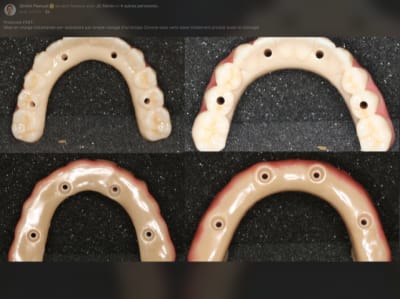

Autres cas de Dimitri : Quad zygo guidé, bridge full zircone tibase collé à l’avance.

Tu es sur facebook, donc tu as peut être vu sa dernière vidéo ( sur son compte et sur le groupe workflow ).

Sinon : quelques capture d’écran .

Je crois que la, il n’y a plus de doute . Full zircone avec rosenscrew, pas de tibase .